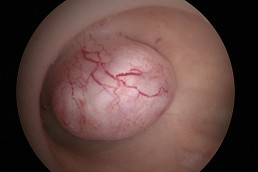

Polipii uterini

Polipii uterini reprezintă proliferări locale ale endometrului (mucoasa ce căptușește cavitatea uterină) și în marea majoritate a cazurilor sunt benigni. Ei pot provoca sângerări anormale, infertilitate sau pot interfera cu implantarea embrionilor în cursul fertilizării in vitro. Polipii endometriali pot fi diagnosticați cu ajutorul ecografiei, iar histeroscopia certifică acest diagnostic. În plus, histeroscopia permite și rezecția și extragerea polipilor endometriali. (fig. 3, 4)